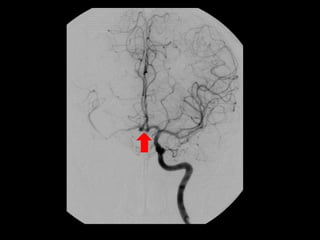

-Anterior temporal branch (best seen in AP view) , a typical

appearance of an anterior temporal branch of the MCA

proximal to the main bifurcation is indicated with the arrow